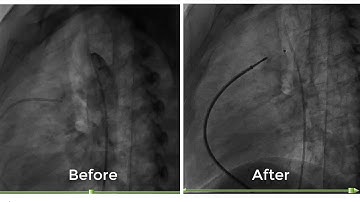

PDA device closure Approximation of distal portion against ampulla